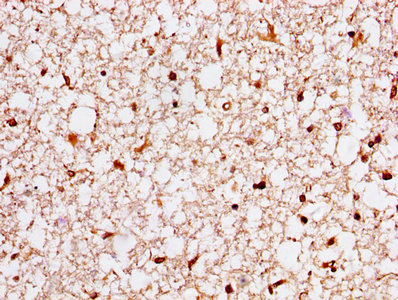

IHC image of CSB-PA02174A0Rb diluted at 1:400 and staining in paraffin-embedded human brain tissue performed on a Leica BondTM system. After dewaxing and hydration, antigen retrieval was mediated by high pressure in a citrate buffer (pH 6.0). Section was blocked with 10% normal goat serum 30min at RT. Then primary antibody (1% BSA) was incubated at 4°C overnight. The primary is detected by a biotinylated secondary antibody and visualized using an HRP conjugated SP system.